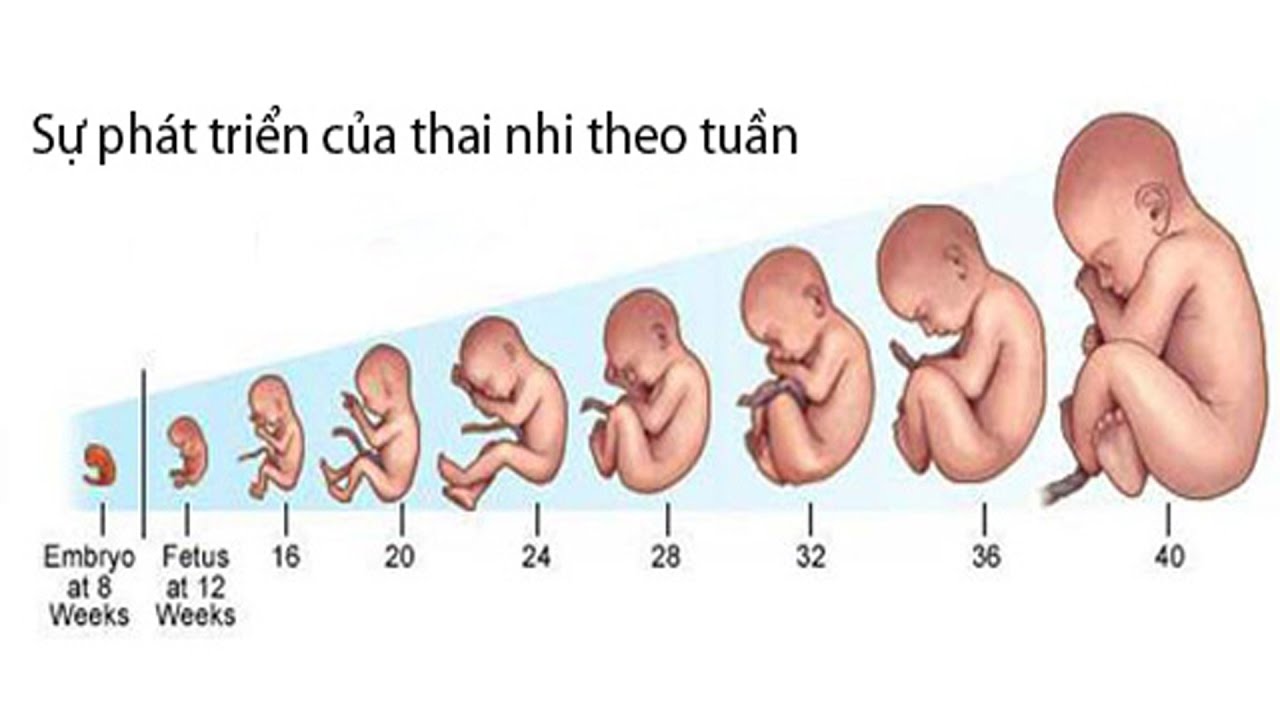

Формирование Плода в Первом Триместре: Важные Этапы